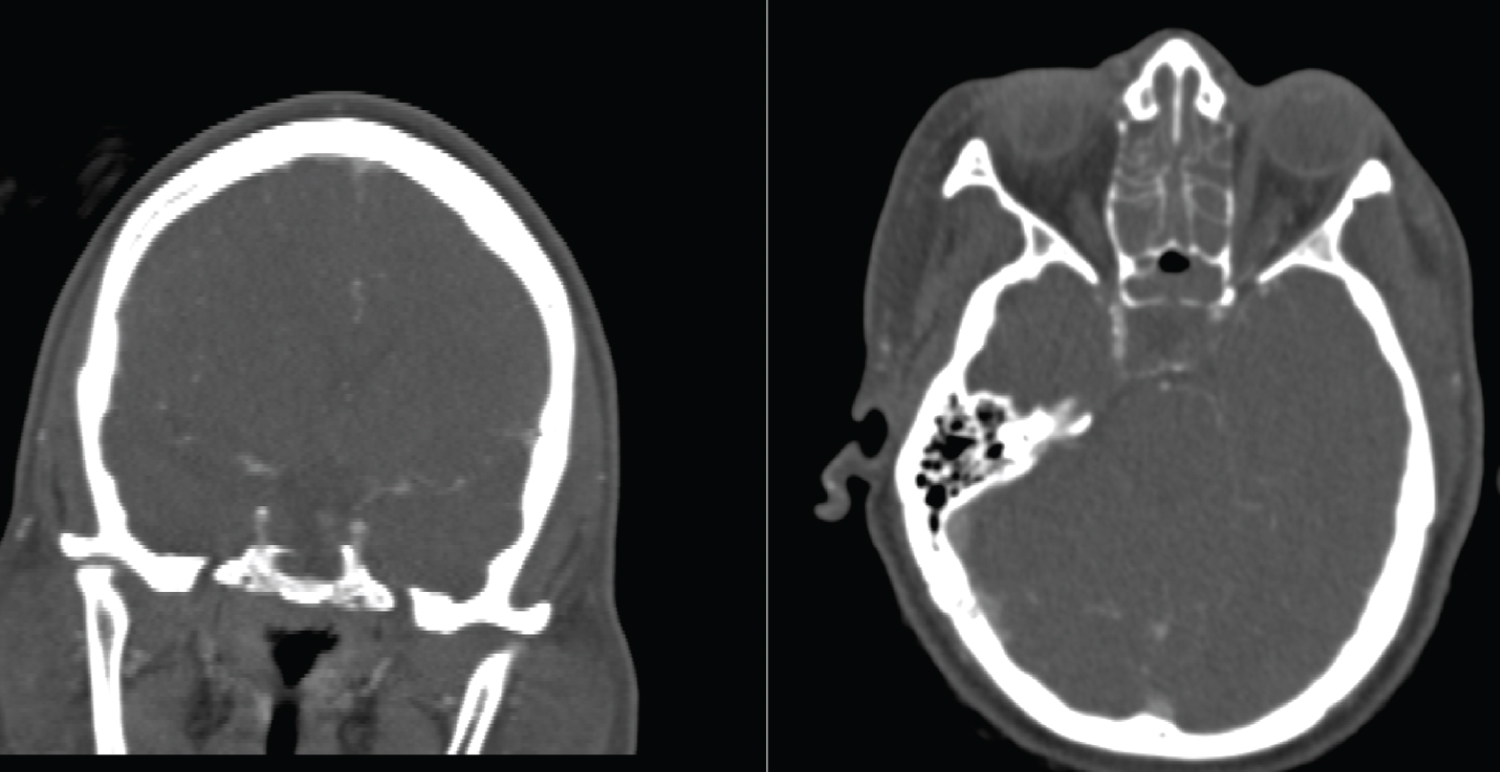

The sella was decompressed, and tissue samples were sent for histopathological evaluation. Intracranial micro-doppler assessment confirmed adequate flow through both ICAs. Immediate post-operative CT angiogram confirmed complete decompression of the sella, and restoration of the normal caliber and flow of the right ICA. (Figure 3).

Figure 3: Coronal and Axial images of CT angiogram done post operatively showing restored flow through the right internal carotid artery. View Figure 3